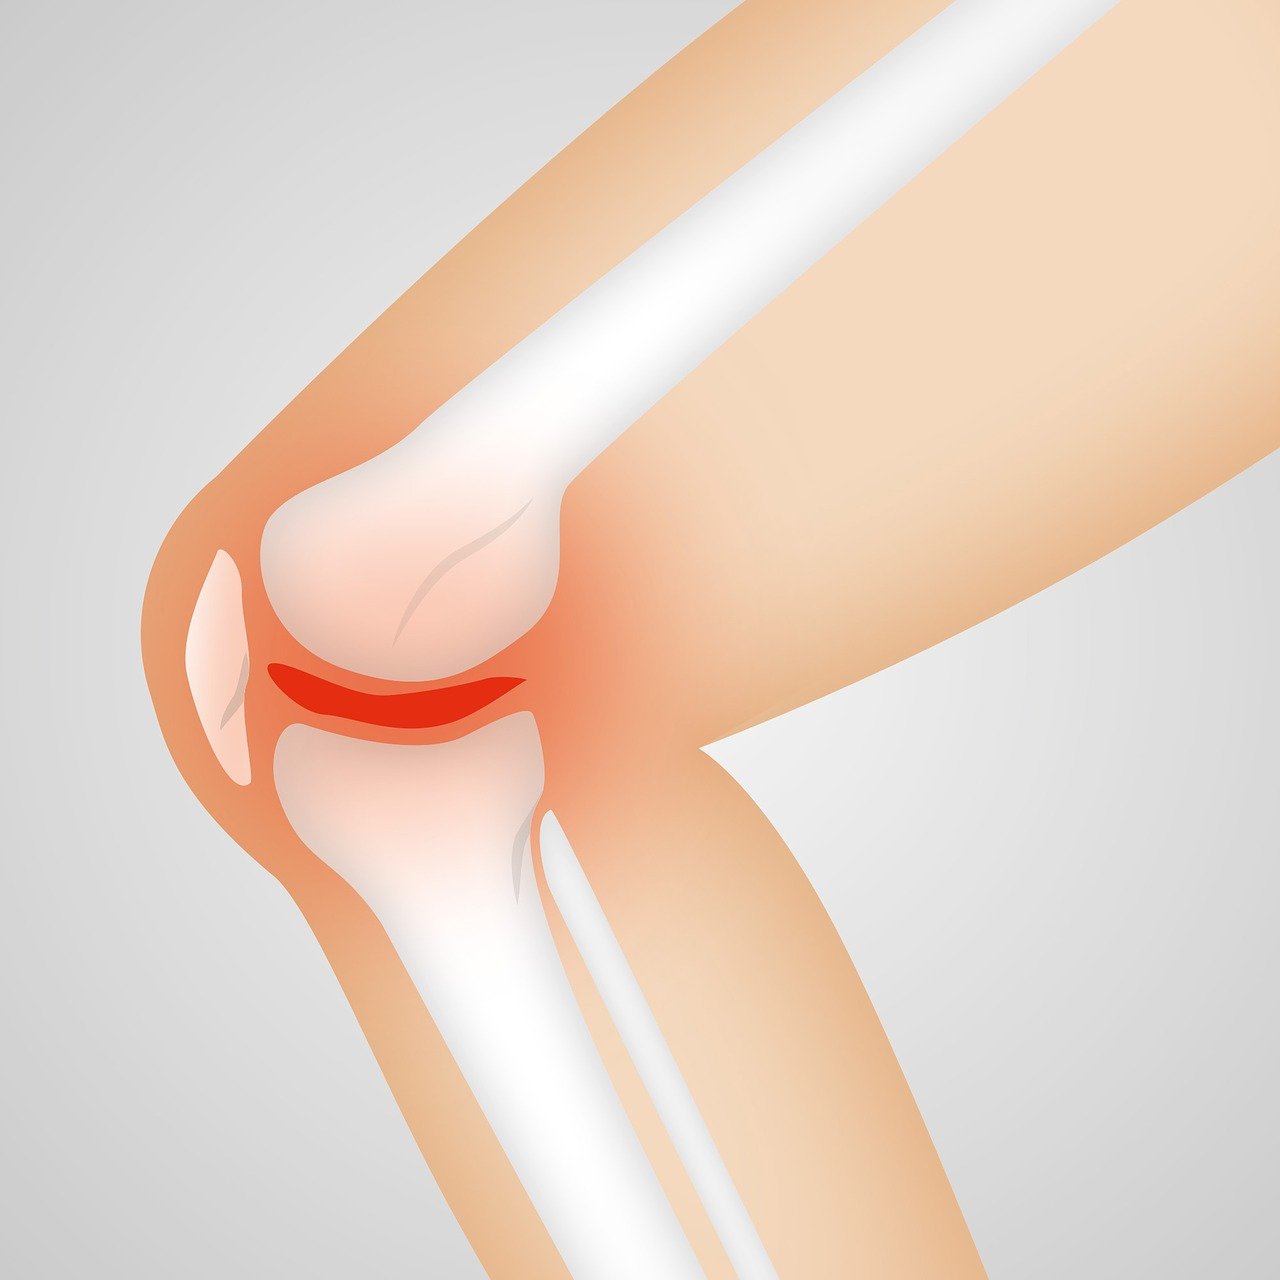

관절을 보호하고 있는 연골의 손상이나 퇴행성 변화로 인해 관절을 이루는 뼈와 인대 등에 손상이 생겨 염증과 통증이 발생하는 질환으로 관절 질환 중에서 가장 많이 발생하는 질환입니다.

3) 부종

염증으로 인해 관절이 붓고 따뜻해질 수 있으며 부종은 관절 주위에 눈에 띄게 나타날 수 있습니다.

5) 관절 소리

관절을 움직일 때 '딱딱'하거나 '뻑뻑'한 소리가 날 수 있으며 이는 연골이 닳아 없어지면서 뼈끼리 마찰이 일어나기 때문입니다.